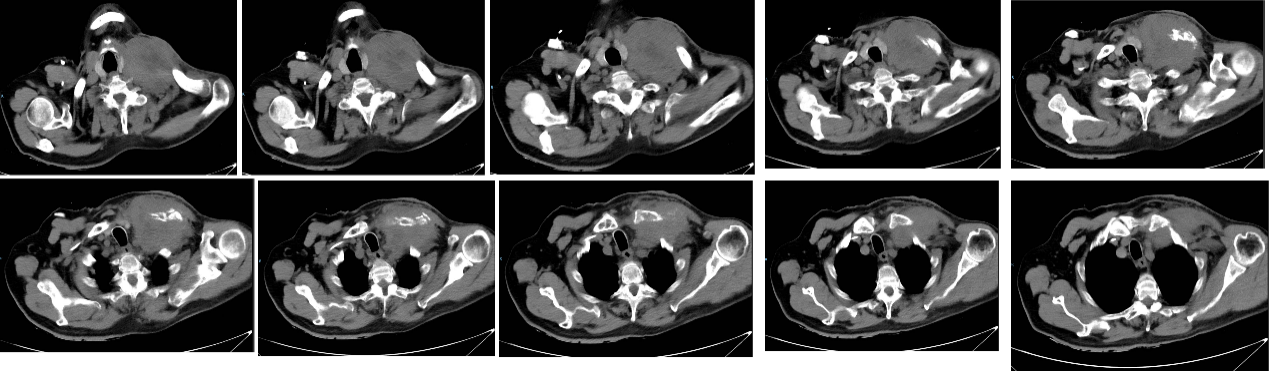

胸部CT增强:左肺上叶肿块(较大截面大小约45×73mm),考虑肺CA可能大。两肺散在结节影,请对比老片,随诊复查。两肺肺气肿,肺大泡。两肺散在条索影,考虑陈旧灶。纵隔散在小淋巴结,请结合临床。

2023-03-15,查胸部CT提示:1. 左肺上叶前段及纵膈内占位性病变,范围较前明显缩小;2. 慢性支气管炎、肺气肿伴两肺炎症;3. 左肺下叶小结节,较前相仿。当地医院予升白、抗感染、吸氧等支持治疗后,稍有好转。

2025-02-27多排CT(胸部+上腹部)平扫:左肺上叶肺CA伴阻塞性炎症,范围较前(2024-12-16)大致相仿,结合临床,必要时结合增强。左锁骨上软组织密度影,左侧锁骨骨质破坏,肿大淋巴结可能,较前明显增大,随诊复查。纵隔及左肺门稍大淋巴结,考虑转移,较前稍缩小。

患者CT示左锁骨上软组织密度影,伴左侧锁骨骨质破坏,考虑较前进展。

2025-03-23患者痰中带血,予卡洛磺纳、氨甲环酸止血后好转。复查胸主动脉CTA:左锁骨下动脉与左锁骨上软组织肿块分界欠清,左锁骨下动脉管腔未见狭窄,结合临床。胸主动脉少许硬化。左肺上叶肺CA伴阻塞性炎症,范围较前(2025-02-26)缩小。左锁骨上软组织密度影,左侧锁骨骨质破坏,肿大淋巴结可能,范围较前大致相仿。纵隔及左肺门稍大淋巴结,考虑转移,较前相仿。左侧胸腔少量积液,较前相仿。两肺实性小结节,部分较前增大,转移待排,随诊。两肺肺气肿、肺大泡。左侧少许胸腔积液,较前增多。心包少量积液,较前相仿。肝内钙化灶。左侧第3.4.5及右侧第3肋骨骨皮质扭曲,较前相仿。两肺散在片絮影及条索影,考虑慢性症/陈旧灶。

介入科会诊建议保守治疗,暂无需行介入止血。氨甲环酸+卡络磺钠治疗后好转。一程放疗结束,复位C1示左肺病灶明显缩小,缩野后继续行二程放疗:95%PGTV 20.0Gy/10f。

2025-05-21,放疗1月后复查:1. 左肺上叶肺CA伴阻塞性炎症,范围较前2025-04-01明显缩小,随诊复查。2. 左侧鼻咽、左侧口咽部、两侧颈部、两侧腋窝、右侧锁骨上、左侧锁骨下及胸壁皮下多发占位伴左侧锁骨骨质破坏,考虑转移,较前左锁骨下病灶稍缩小,两侧腋窝及胸壁病灶较前新增。3. 纵隔及左肺门稍大淋巴结,考虑转移,较前部分增大。3. 两肺多发结节,部分较前增大,考虑转移,随诊。4. 两肺肺气肿、肺大泡。5. 两肺散在片絮影及条索影,间质性改变,较前明显进展。6. 右肺下叶条样高密度影,支气管粘液栓?7. 肝脏多发低密度灶,考虑转移。8. 右肾囊肿。